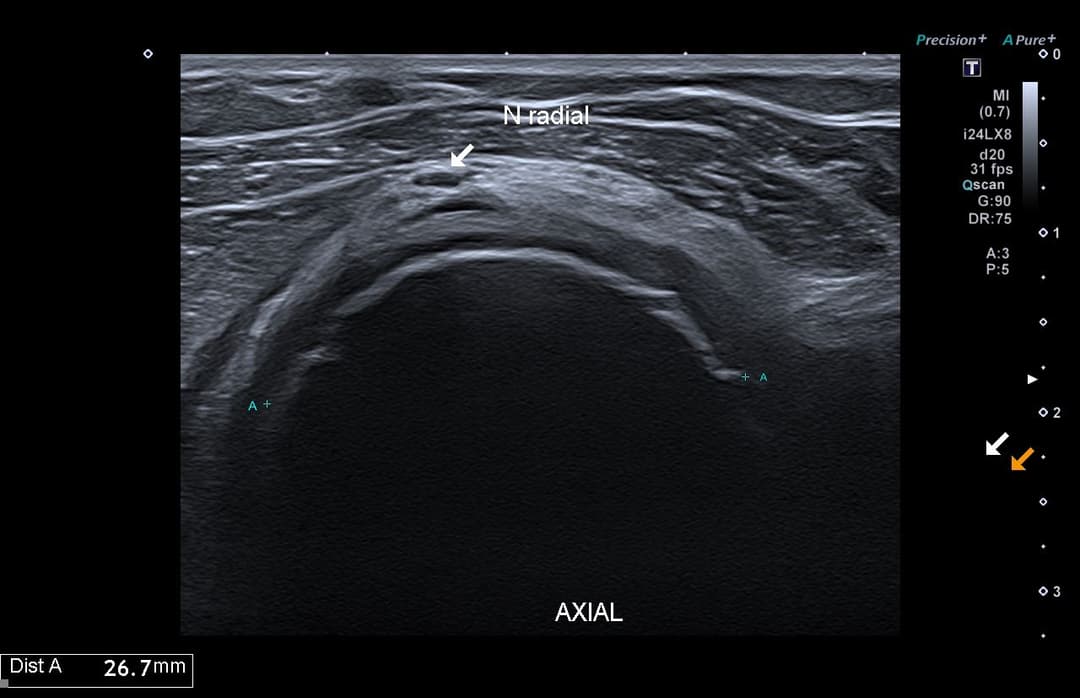

Échographie

Volumineuse structure osseuse additionnel qui s'avérera être un ostéochondrome de la tête radiale.

Compression du nerf radial qui présente une perte de son parallélisme et un épaississement hypoéchogène à son passage en regard de la structure.